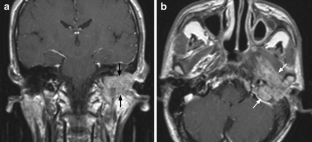

Fig. 1